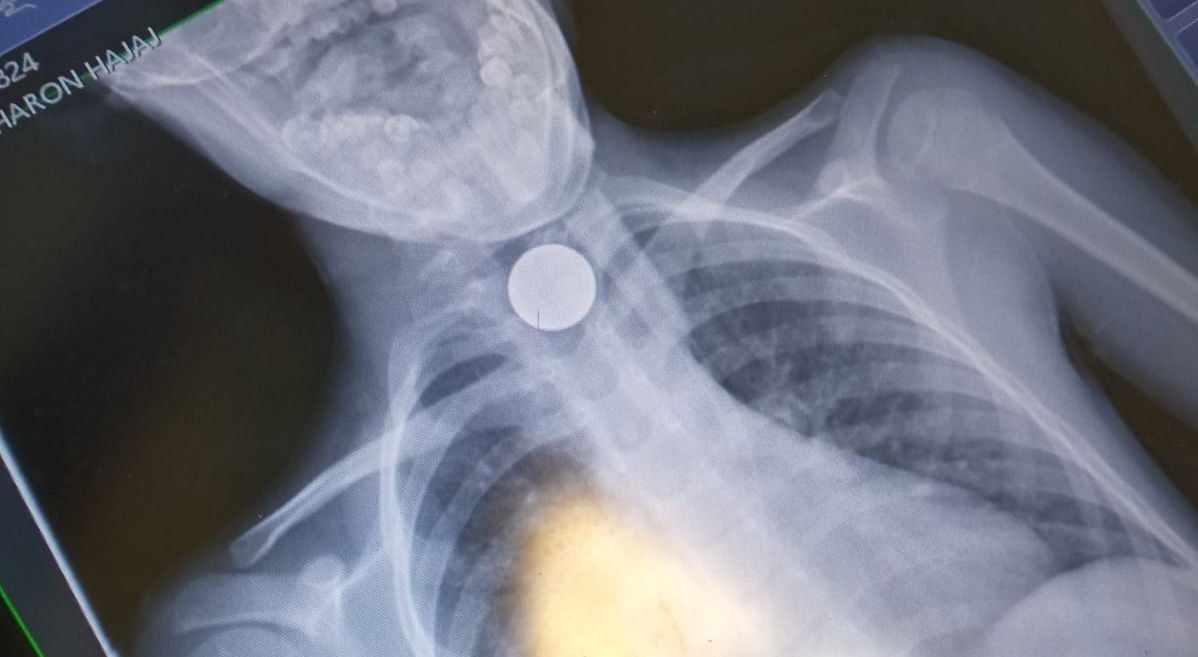

ילד חרדי, כבן 7, נחנק הערב (שלישי) בביתו שבבני ברק, לאחר שבלע מטבע של 10 אגורות.

כוחות ההצלה שהוזעקו לבית המשפחה, עודכנו כי המטבע נתקע לו בקנה הנשימה, ומיהרו לייצב את מצבו.

אפי פלדמן ראש סניף איחוד הצלה בבני ברק סיפר: "כשהגעתי למקום נמסר לנו כי הילד נחנק ממטבע של 10 אגורות שנתקע לו בקנה הנשימה. פיניתי אותו באמבולנס איחוד הצלה למרכז הרפואי מעייני הישועה תוך כדי שייצבנו את מצבו".